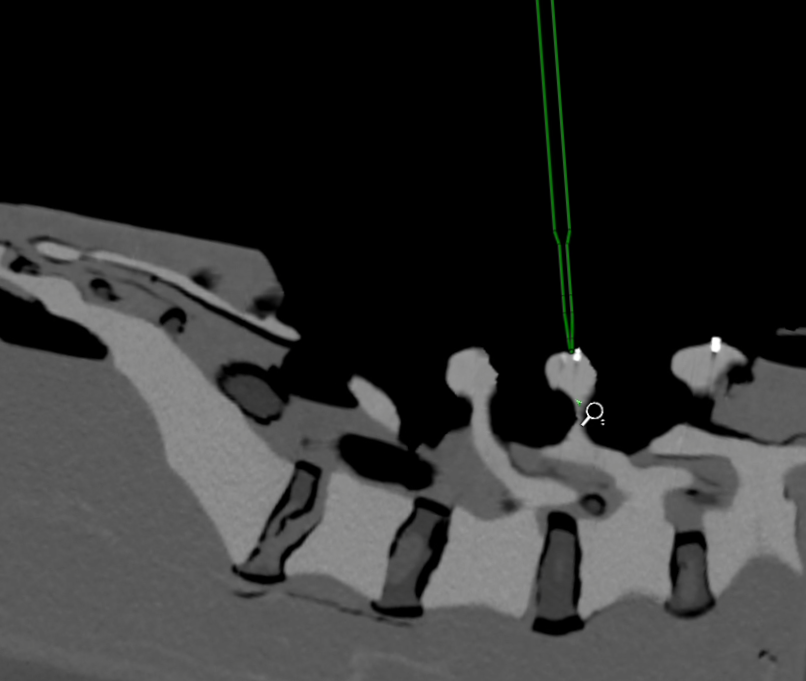

Computer-aided surgery (CAS), especially in spinal procedures, benefits greatly from advancements in imaging, navigation, and robotics. This research develops novel intraoperative registration techniques for fluoroscopic images to enhance spatial awareness and real-time guidance. By integrating tracking data with registered images, the system ensures accurate instrument localization, precise implant placement, and improved navigation—crucial for minimizing complications and enhancing outcomes in minimally invasive surgeries.

- Image Registration